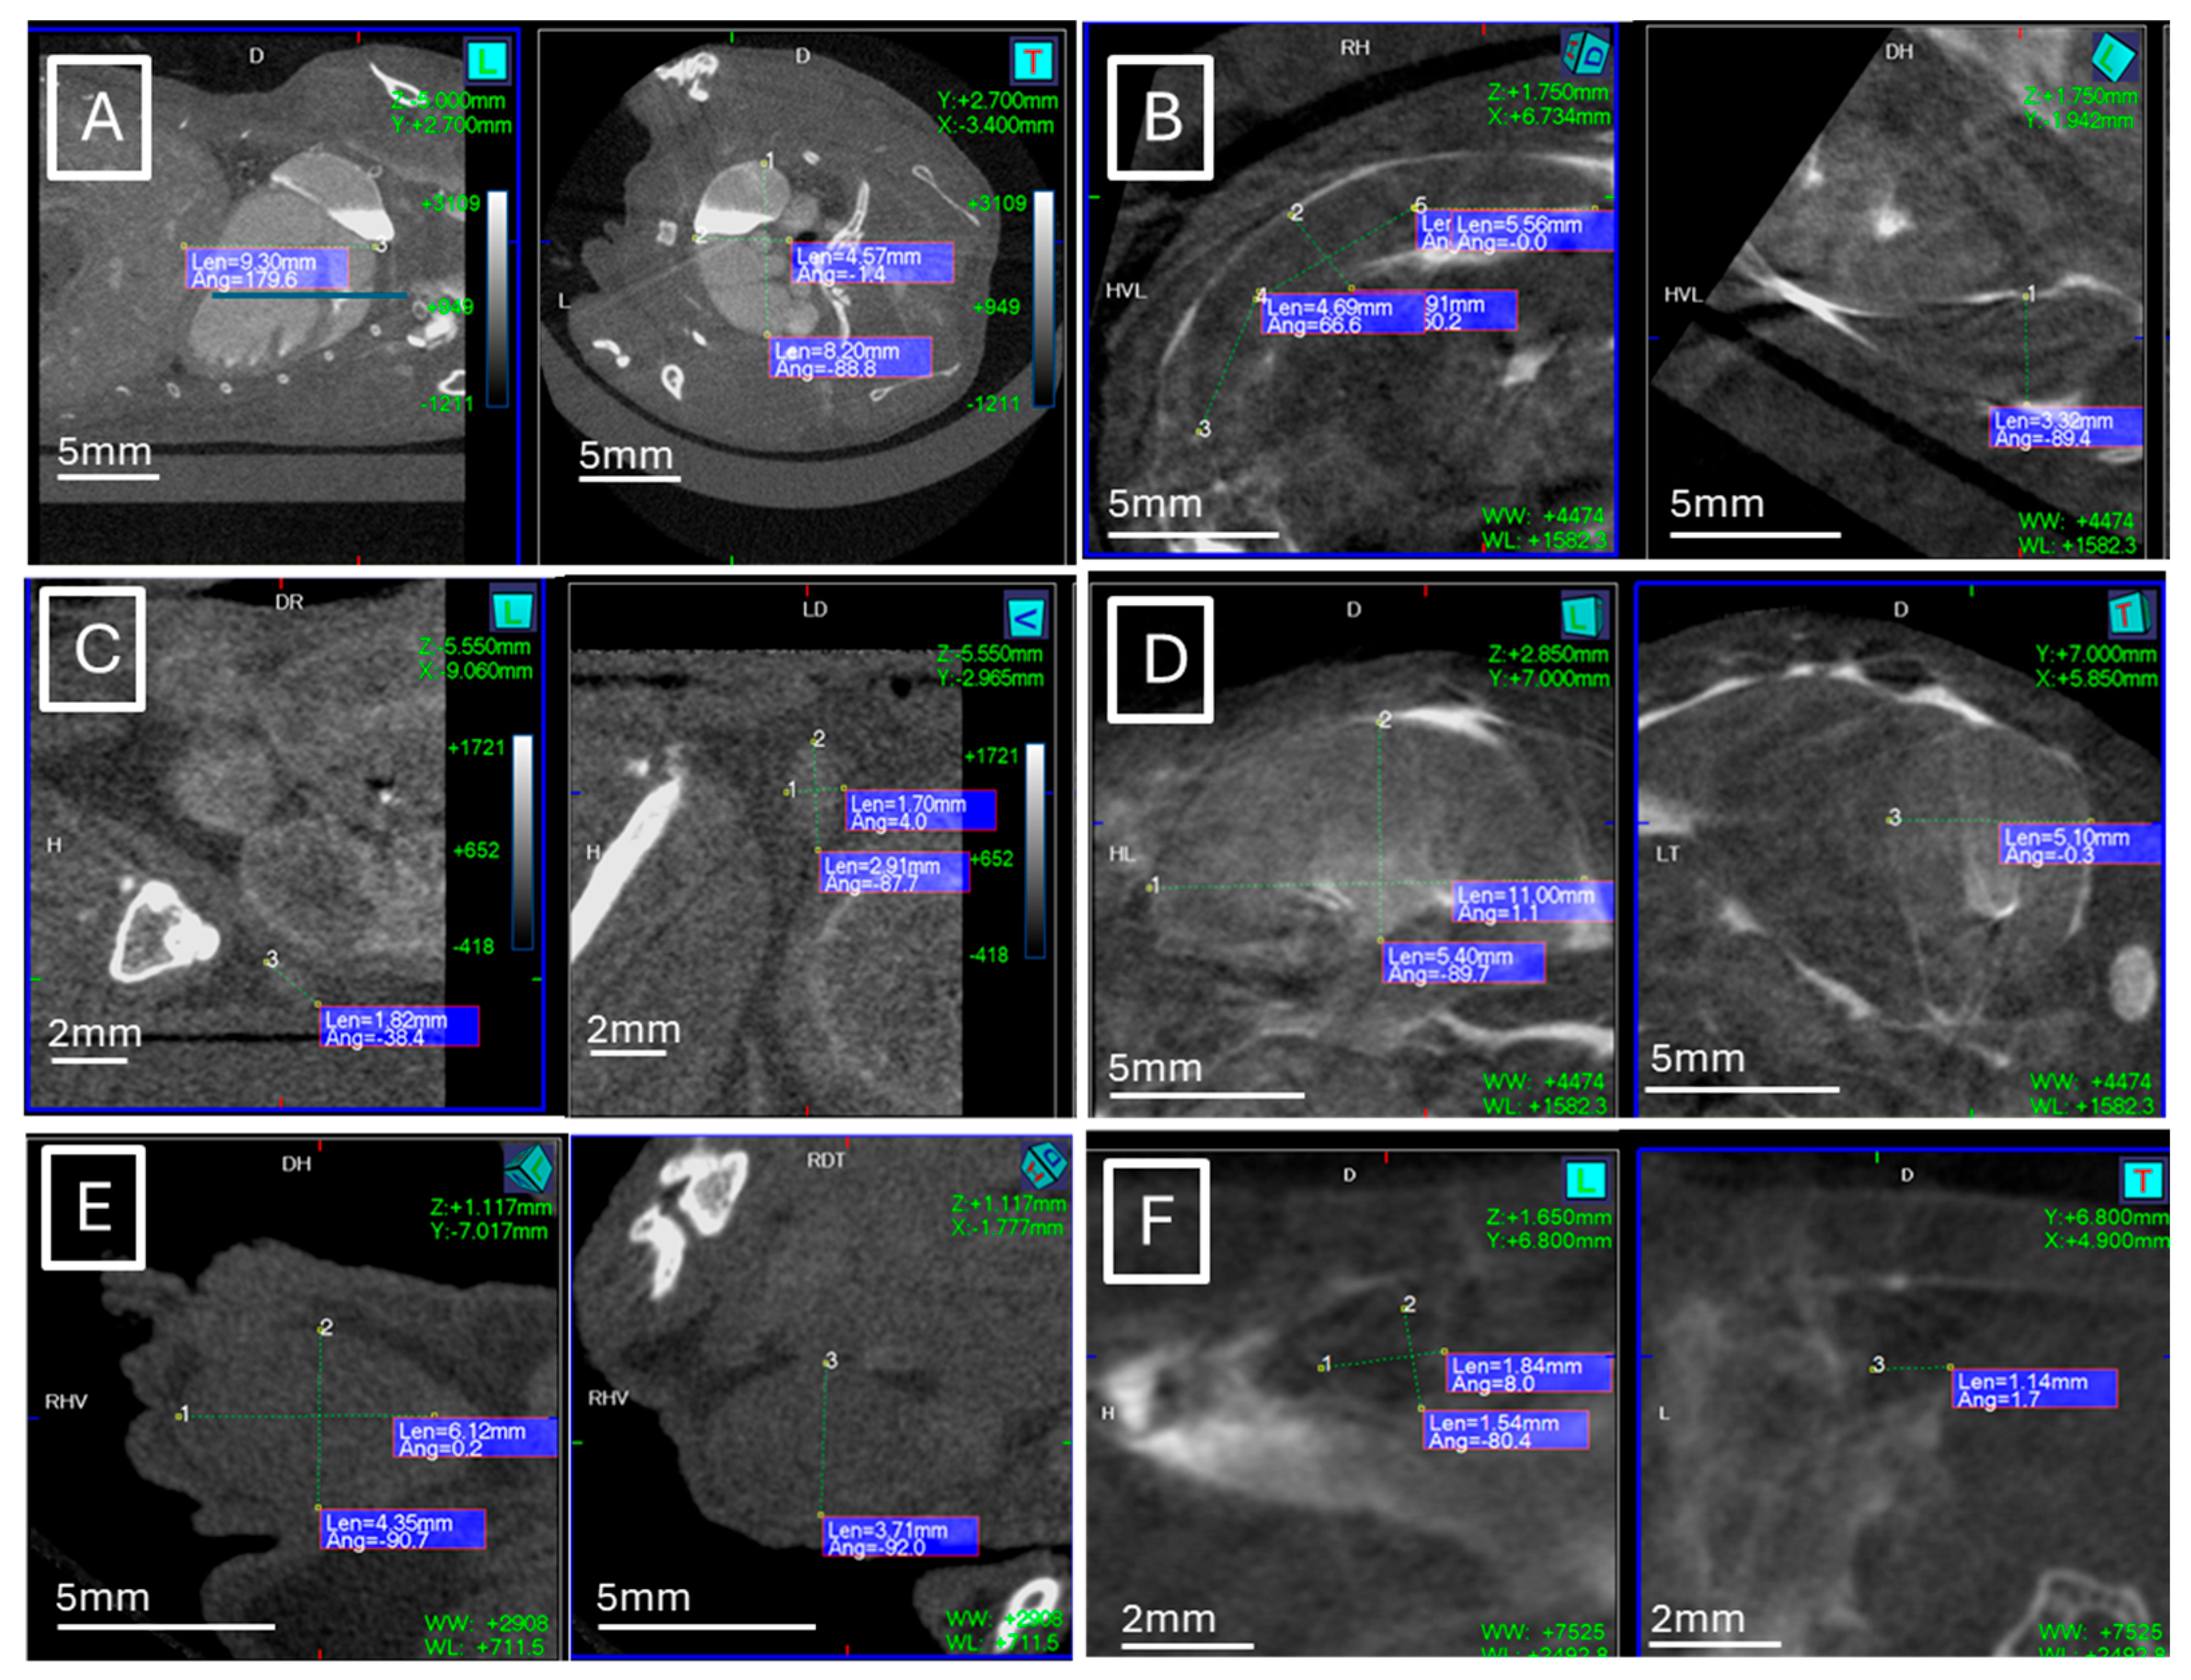

Figure 1 and Figure 2 show examples of ultrasound and microCT diameter measurements. Figure 3 shows examples of manual segmentation.

Figure 2.

Example of maximal diameter measurements (dotted lines) in microCT studies. (A) Heart in coronal (left) and axial (right) views, (B) spleen in axial (left) and coronal (right) views, (C) left lymph node in sagittal (left) and coronal (right) views, (D) left kidney in sagittal (left) and axial (right) views, (E) left testicle in sagittal (left) and coronal (right) views, (F) left ovarian in sagittal (left) and axial (right) views.